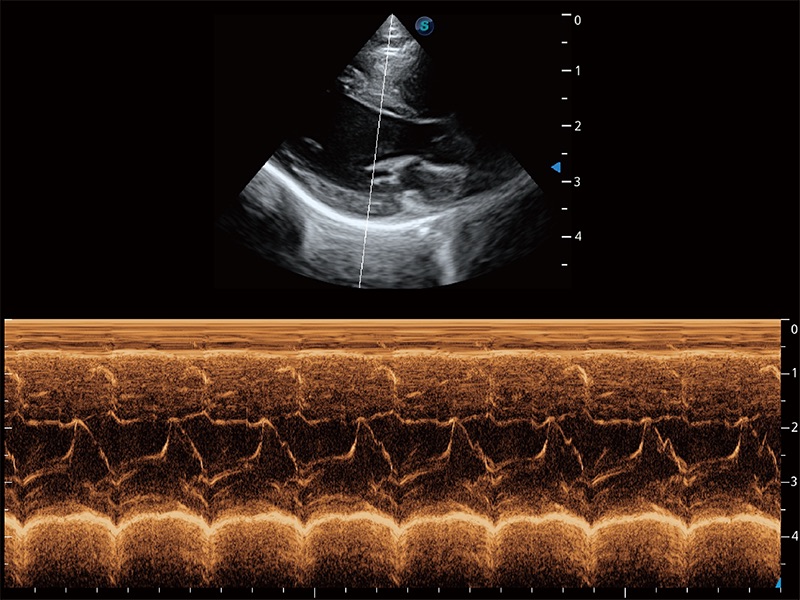

通過(guò)360度任意調(diào)節(jié)3條M型取樣線,在同一心動(dòng)周期上觀察心臟不同位置的運(yùn)動(dòng)曲線,得到準(zhǔn)確的心功能測(cè)量數(shù)據(jù),有效評(píng)估心肌運(yùn)動(dòng)及左心室功能。